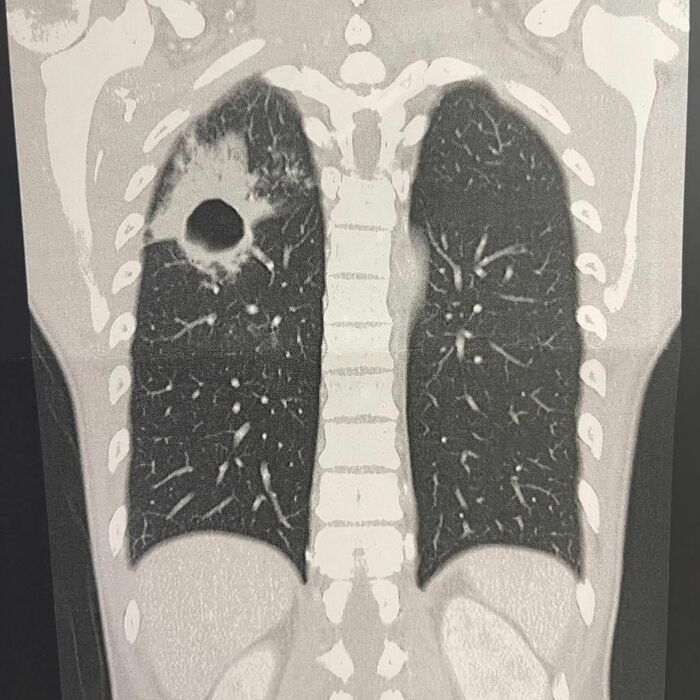

さらに、投稿では肺膿瘍を患っていたときのものと見られる、肺のX線写真も公開。

写真を見ると、片方の肺の上部に大きく穴が空いているのがわかります。

河井さんは投稿文で「肺に穴が空いてから約半年。改めて健康の有り難さを感じました。」と振り返っていました。

このX線写真にも多くの反響を呼び、SNSでは「撃たれとる」「インパクトが凄すぎる」「穴ってこんなに大きいの?撃たれた?って感じ」「肺の衝撃写真は一生忘れません」と驚きの声とともに、「穴が塞がって良かったですね」「ゆずるさん完治してほんとうによかった!!」「もう穴開かないように気をつけて元気にいてくださいね」と河井さんの回復を喜ぶ声がたくさん寄せられています。